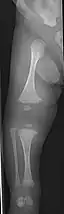

The main symptom of osteogenesis imperfecta is fragile, low mineral density bones; all types of OI have some bone involvement.[5] In moderate and especially severe OI, the long bones may be bowed, sometimes extremely so.[28] The weakness of the bones causes them to fracture easily—a study at the Endocrine Unit at the National Institute of Child Health in Karachi, Pakistan found an average of 5.8 fractures per year in untreated children.[29] Fractures typically occur much less after puberty, but begin to increase again in women after menopause and in men between the ages of 60 and 80.[1]: 486

- Type V – Having the same clinical features as type IV, it can be clinically distinguished by observing a "mesh-like" appearance to a bone biopsy under a microscope. Type V can be further distinguished from other types of OI by the "V triad": an opaque band (visible on X-ray) adjacent to the growth plates; hypertrophic calluses (abnormally large masses of bony repair tissue) which form at fracture sites during the healing process; and calcification of the interosseous membrane of the forearm,[50] which may make it difficult to turn the wrist.[1]: 429 Other features of this condition may include pulled elbow, and, as in other types of OI, long bone bowing and hearing loss.[64] Cases of this type are caused by mutations in the IFITM5 gene on chromosome 11p15.5.[64][49] The separation of type V from type IV OI, its clinical type, was initially suggested even before its genetic cause was known, by Glorieux et al. in 2000.[50][65] Type V is relatively common compared to other genetically defined types of OI—4% of OI patients at the genetics department of the Brazilian Hospital de Clínicas de Porto Alegre were found to have it.[66]